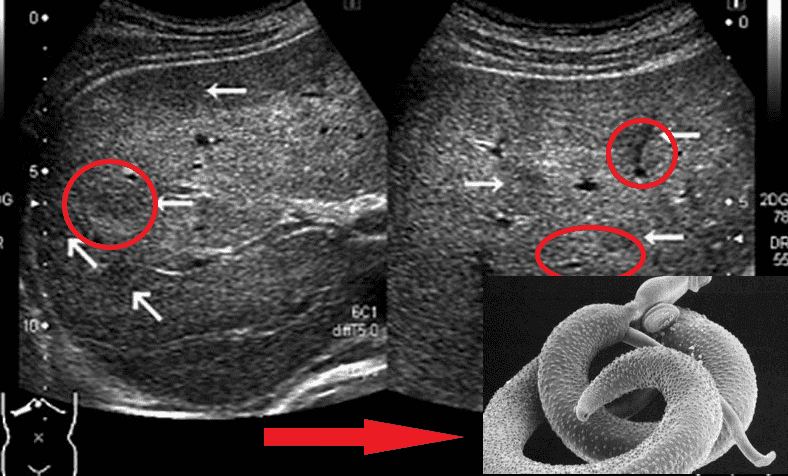

Acabo de hacer una autopsia ayer: una mujer, 50 años. Ella falleció de insuficiencia cardíaca. Entonces, ¿qué tienen que ver los parásitos con esto? Y a pesar del hecho de que su desperdicio conduce a la interrupción del trabajo de todos los órganos, incluido el corazón. Encontré una gran cantidad de parásitos en sus intestinos. Con tales "vecinos", desafortunadamente, el hombre no puede vivir mucho tiempo.

Otro caso: hombre, 61 años. Falleció de cirrosis del hígado. Los familiares creen que el alcohol tiene la culpa. Solo que no bebía mucho y no hay signos de daño por el alcohol en el hígado, pero los parásitos simplemente se comieron el hígado, encontré cientos de pasajes a lo largo de los cuales los gusanos se movían.

He sido patólogo durante muchos años. ¡He visto cosas que nos ponen los pelos de punta! La gente subestima los riesgos, piensa que los parásitos son gusanos que viven en los intestinos. Pero no es así. Hay muchos tipos de parásitos. Por ejemplo, los hay diminutos, pero muy tóxicos. Envenenan su cuerpo, penetran en el torrente sanguíneo, el corazón, lo agotan con sus toxinas, provocan isquemia, insuficiencia cardíaca, hipertensión y, como resultado, ataques cardíacos y derrames cerebrales. ¡Se asientan en los pulmones, el hígado, penetran en el cerebro e incluso los órganos viven en los ojos!

Los representantes de los helmintos que afectan los órganos vitales son Taenia solium, echinococcus (Echinococcus granulosus), trichinella (Trichinella spiralis). Echinococcus es una etapa larval de un helminto del género Echinococcus. Y esto no es todo tipo de parásitos.